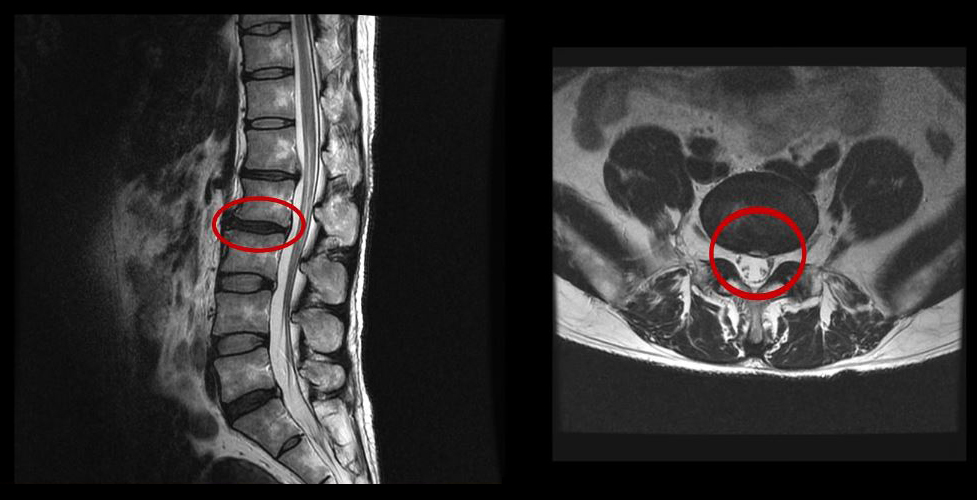

그런데 이 환자분의 MRI를 보면 여러 마디에 퇴행성디스크가 있습니다.

이 환자분은 MRI상으로 거의 대부분 마디의 디스크가 퇴행되고 수핵이 밀려나와 있으며, 정상적인 허리 마디는 4-5번 하나 정도입니다. 그렇기 때문에 MRI만 보면 아마 대부분의 병원에서 허리디스크탈출 또는 퇴행성디스크로 인한 허리통증 및 다리통증으로 진단하고 치료할 것입니다. 이분도 그래서 20년간 그런 치료를 무수히 많이 받았으나 그 어떤 치료도 별 도움이 되지 않았습니다.

이 환자분처럼 오랜 기간 만성적인 허리통증이 있고, 엉덩이가 저리면서 심지어는 양쪽 다리저림까지 있는 환자분들이 많습니다. 그런데 이 환자분의 MRI를 보면 여러 마디의 퇴행성디스크, 디스크탈출, 황색인대의 두꺼워짐, 후관절의 퇴행 등 다양한 병변들을 가지고 있는 걸 볼 수 있는데요. 그렇기 때문에 많은 병원에서 이분을 디스크로 진단하고 거기에 따른 치료가 이루어졌습니다. 그러나 저희가 보기에는 이분의 MRI상으로 보이는 여러 마디의 디스크 문제가 이 환자분이 갖고 있는 증상을 설명할 수 없었습니다.

만성적인 허리통증은 그 원인을 찾기가 매우 힘듭니다. 왜냐하면 만성 허리통증의 대부분은 근육의 기능 문제가 원인인데, 근육의 기능 문제는 MRI상으로는 보이지 않기 때문입니다. 또 양쪽 다리가 저린 이유도 MRI만으로는 알 수 없습니다.